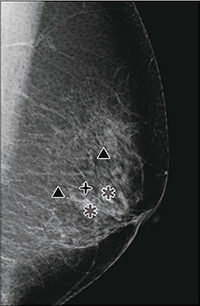

Cenovaはデジタル式乳房X線撮影装置「Selenia」,または「Selenia Dimensions」で撮影したマンモグラフィ画像を基に,石灰化や腫瘤などを疑う関心領域の検出支援情報を画像ビューアなどに送信する装置です(図1)。Cenova1台で最大4台までの撮影装置と接続が可能です。

図1 Cenovaマーキング例